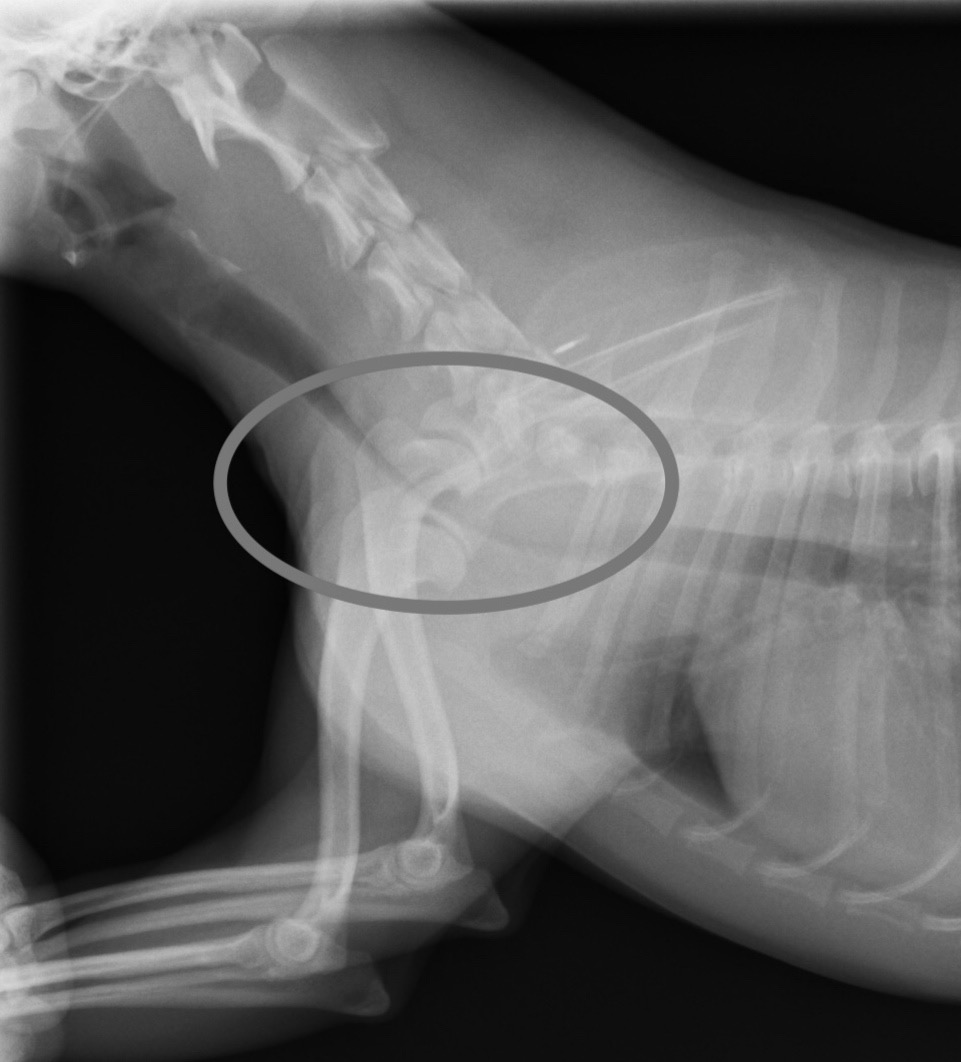

手術前のレントゲン画像。 ◯内の狭窄した気管が確認されます。